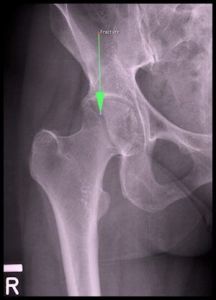

“Femur Boyun Kırığı Nedir?” üzerine bir yorum